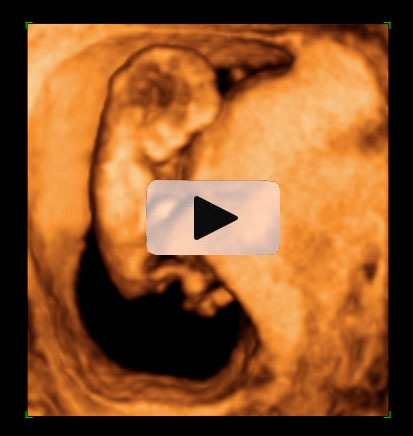

Ecografía semana 12 de embarazo gemelar

Ecografía 4D de gemelos de 12 semanas "contrapeados": Cada uno de los bebés está con la cabeza en una dirección, tal y como podemos visualizar en el ultrasonido. Uno de los gemelos se mueve al final de las imágenes de la ecografía mientras su hermano descansa.

Ecografía en 4D de gemelos de 12 semanas "contrapeados"

Cada gemelo está con la cabeza en una dirección, tal y como se aprecia en esta ecografía en 4D. Los dos fetos "contrapeados" tienen bolsas y placentas independientes. Destaca el movimiento del gemelo que aparece en la parte superior de la imagen: pareciera que se "arranca" a bailar al final del vídeo, mientras que su hermano permanece más tranquilo en su bolsa.